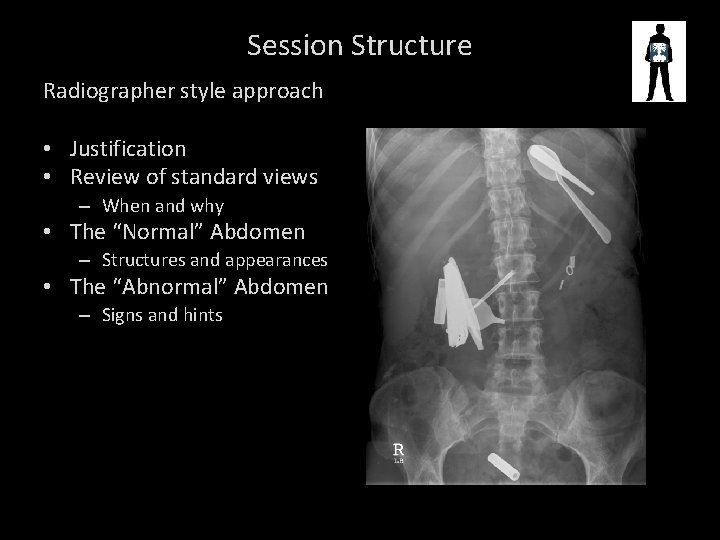

Session Structure Radiographer style approach • Justification • Review of standard views – When and why • The “Normal” Abdomen – Structures and appearances • The “Abnormal” Abdomen – Signs and hints